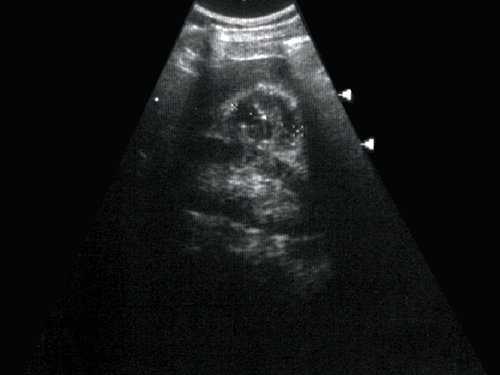

Основными симптомами кистозной почечно-клеточной карциномы при УЗИ являются: 1) внутренняя структура образования имеет неоднородную эхоструктуру в виде чередования гипо-, изо- и гиперэхогенных участков; 2) выявляется массивная неровная, возможно обызвествленная, капсула, контур которой не всегда четкий; 3) образование может выглядеть как многокамерное жидкостное или гипоэхогенное с эхогенным компонентом, который определяется обычно в виде перегородок; 4) выявление в полости образования внутреннего тканевого содержимого, расположенного чаще всего на периферии образования; 5) выраженная деформация чашечнолоханочной системы пораженной почки; 6) при прорастании опухолью соседних органов и тканей отмечается ограничение дыхательной подвижности почки; 7) возможна визуализация тромба в просвете нижней полой или почечной вен, что имеет существенное значение для дальнейшего плана обследования и тактики лечения; 8) отсутствие эффекта дорзального усиления (рис. 1, 2).

Рис. 1. Эхограмма. Кистозное образование правой почки. Гистологически - почечно-клеточная кистозная карцинома.

Многокамерное образование неправильной формы, с неровной толстой стенкой, с вкраплениями кальция, множественные перегородки с локальными утолщениями. Выраженная неоднородность внутренней эхоструктуры в виде чередования гипо-, изо- и гиперэхогеных участков.